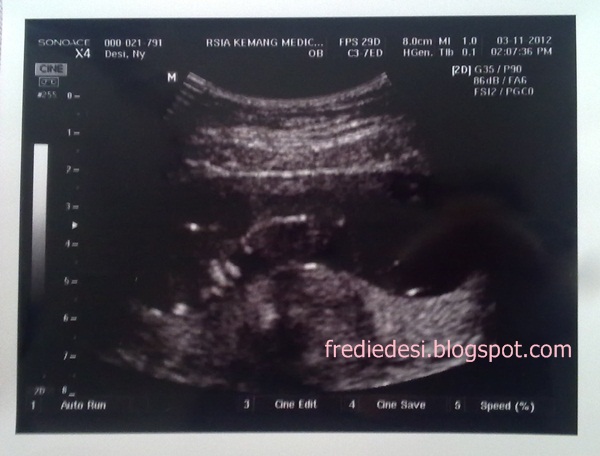

Ini foto USG dede pas 12W2D bulan November ^_^

Mulai rekam dedek dari pas 12W2D. sayang sih ya ga pas dari pertama. Apalagi pas kontrol 9W2D bebi ga difotoin USG-nya. Sayang kata dokternya :( Gapapa ya nak, mending telat daripada ga ada sama sekali :)

USG kali ini sama dr. Hari P. Rahardjo. Masih di KMC. Kontrol sama beliau enak, komunikatif, dan baiiiiik bener. Sampe suka gambar-gambar di kertas kalo jawab pertanyaan pas kita nanya ini itu. Setiap datang dan pulang pun beliau suka memberi salam: Assalamualaikum. Huaaaa gimana ga adem kan yah?

Tipikalnya dr. Hari ini sama kaya aku kayanya rame, hihi, jadi cocok dan klop deh. Trus kalo USG lamaaaa dan detail. Mau nugguin kita yang penasaran minta dilamain. Gara2 mau liat muka dede(yaoloh neng ini masih 12W mana keliatan, ya maaf hihi...).